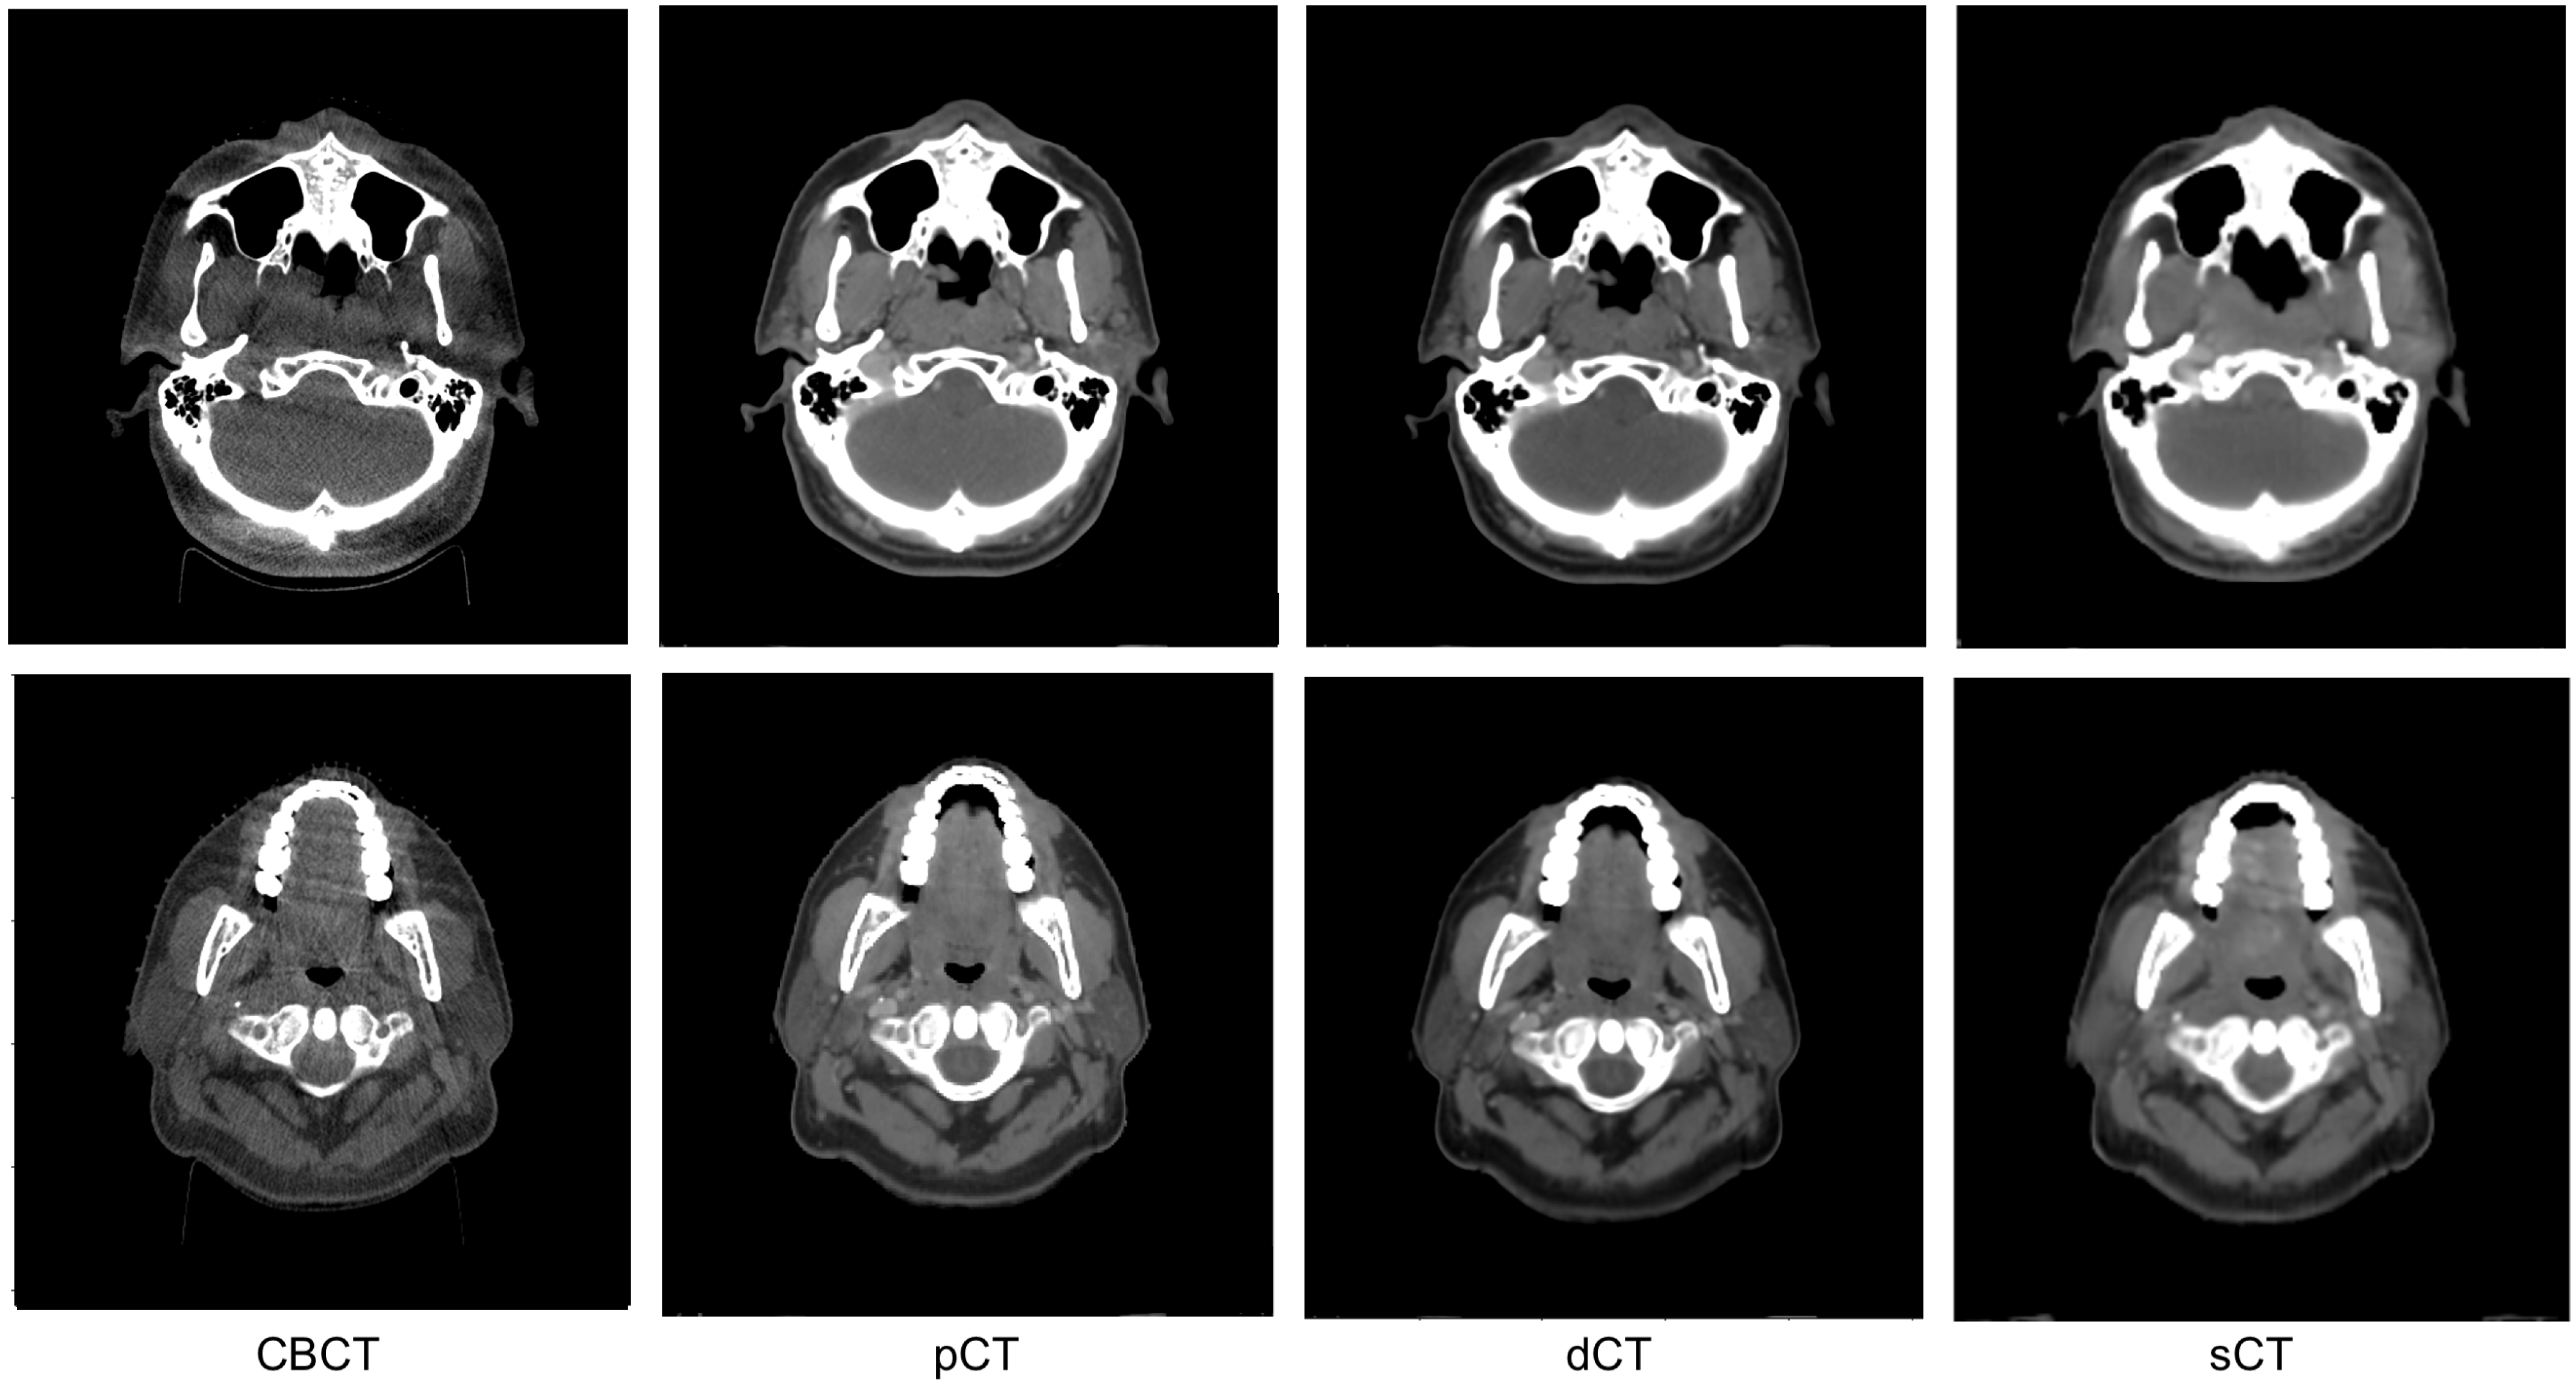

3. Results

3.1. Image Quality Evaluation with Quantitative Metrics

3.2. Image Quality Evaluation in Preserving Anatomy